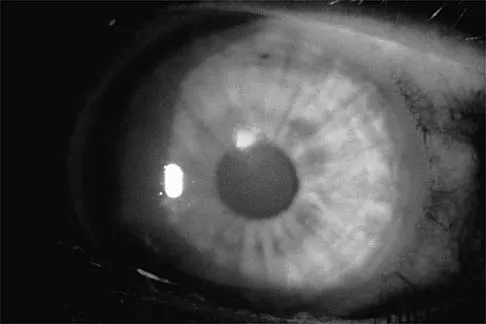

Question 94

A college basketball player is struck in the eye by a player's hand while driving to the basket. Fluorescein evaluation reveals the injury shown in Figure 18. Management should consist of